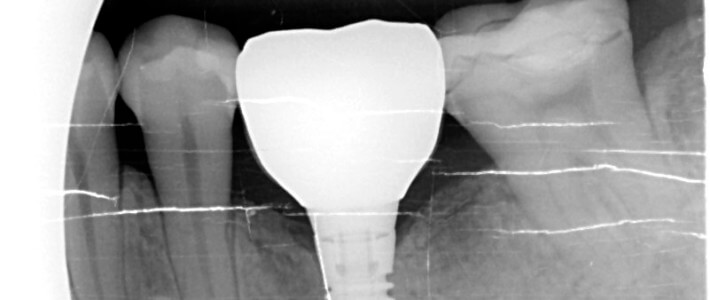

植牙前注意事項 1.植牙手術前儘量維持口腔衛生清潔。 2.植牙手術前一星期及術後Read more